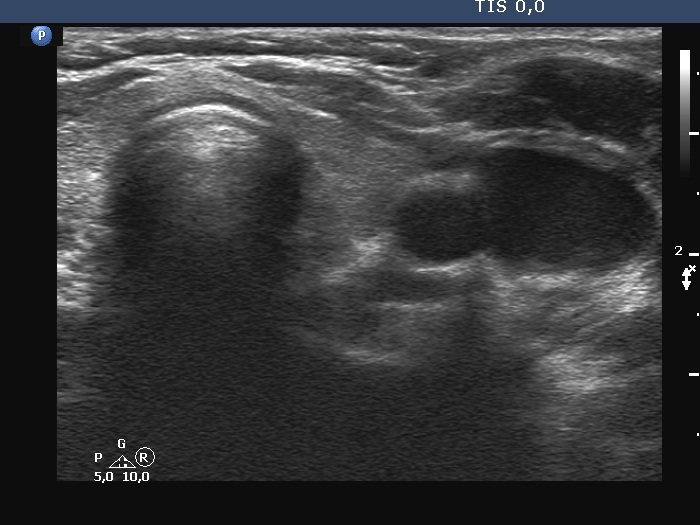

Right lobe, longitudinal scan

Left lobe, transverse scan. There are some minimally hypoechoic fields within this lobe.